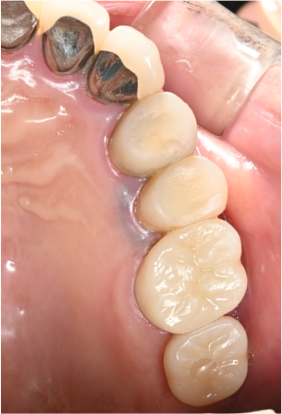

治療後

| 年齢・性別 | 60代 男性 |

| 主訴 | 右上6が他院にてインプラントできないと言われたため 当院にてインプラン ト治療を希望 |

| 治療内容 | 右上6を抜歯し、3か月後にインプラント埋入を行った。 上顎洞底まで骨量が 不足していたため、ソケットリフトを同時に行った。埋入後3か月後に上部構 造(ジルコニア)を装着した。 |

| 治療期間 | 6ヶ月・10回 |

| 治療費用 | 総額:495,000円(税込) 【内容】 インプラント埋入手術 270,000円 ソケットリフト 50,000円 インプラント被せ物 130,000円 |

| リスク・副作用 | ・外科処置が必要 ・自費診療(保険適用外)となる ・ソケットリフト後、稀に上顎洞内感染の可能性がある |